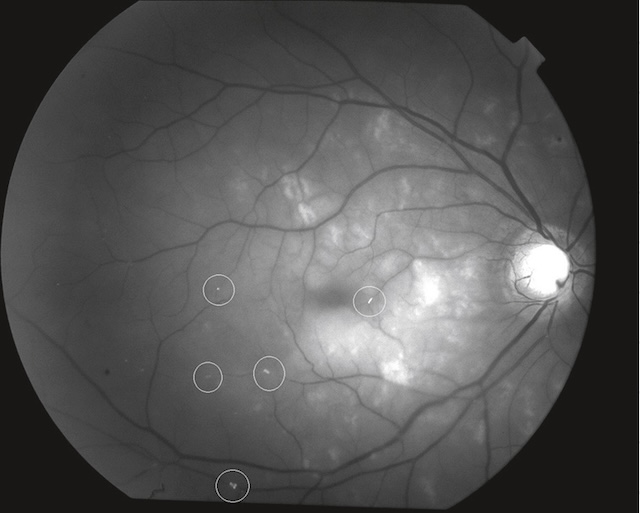

L’œdème papillaire est le signe diagnostique initial le plus évident (fig. 16.12) et le plus important de la NOIA. Il peut ne toucher qu’un secteur ou être total, en fonction du territoire de l’ACP occluse; la papille a souvent une coloration pâle et il existe fréquemment une ou plusieurs hémorragies en flammèches sur le bord papillaire (fig. 16.13).

A. œdèmes papillaires associés à des hémorragies en flammèches localisées en nasal de la papille. B. œdèmes papillaires associés à des hémorragies en flammèches plus diffuses.

Sur l’image A, on distingue un disque optique pâle avec une atténuation du réseau vasculaire périphérique, traduisant une ischémie chronique. La papille montre une atrophie optique secondaire, sans signe inflammatoire aigu. En revanche, l’image B illustre une phase aiguë de neuropathie optique ischémique antérieure, avec un œdème papillaire important, des hémorragies en flammèche autour du nerf optique, et une hyperémie marquée. Les bords de la papille sont flous, envahis par l’œdème, témoignant d’une atteinte vasculaire brutale et sévère du nerf optique.